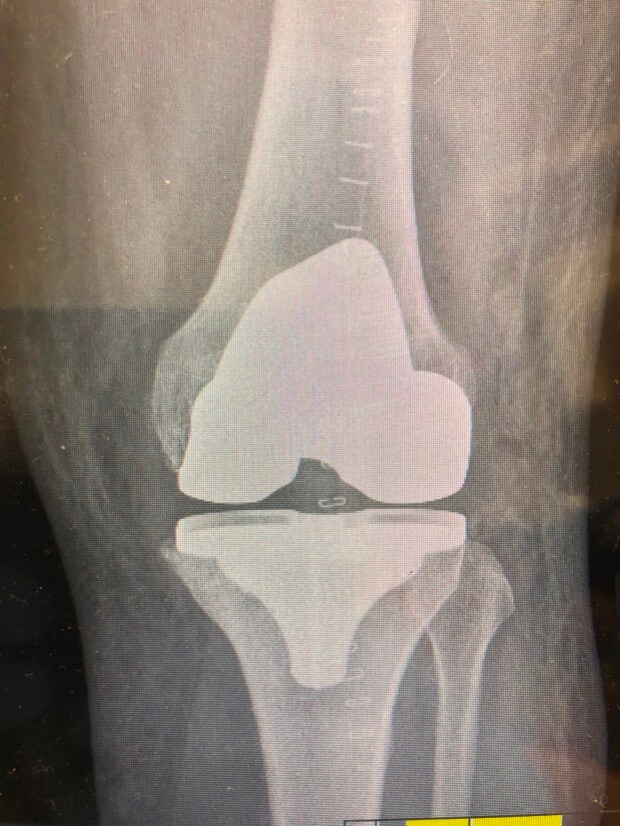

1. Evening TT’ers I’m one week into recovery from having total knee replacement surgery on my left knee. I’m wondering if anyone else out there has had the same surgery and can provide some advice on how long it took after surgery before you were back on the golf course or at least swinging a club. Are there any pitfalls I should avoid? All advice welcome including tongue in cheek to cheer me up!!! Cheers………..Steve

3. Stephen, I've been there - I've got similar X-rays, though mine have random bits of metal from earlier ACL's. Right knee for me. Right knee is "better" as the loading through the swing is more intense on the left knee for right handers. One week in can be a low point. No point in being a hero - take whatever painkillers they give you!! Stairs will be an issue for some considerable time I'm afraid. You will, however, be able to use stairs to strengthen your muscles. Be diligent about your physio and to get access to an exercise bike of some description! When allowed, I did lots of walking and found it helped. I had my op in the November and was ready for the Driving Range the following March. Some say they were back on the golf course six weeks after the op - I would consider that to be a very risky strategy. It's a major reconstruction and it takes time to heal. The numbness wears off eventually but don't expect it to be exactly like a natural knee - it's good, but it's not that good! Oh, and be prepared to be stopped by Security at every airport - You'll set of the metal detector alarms!!